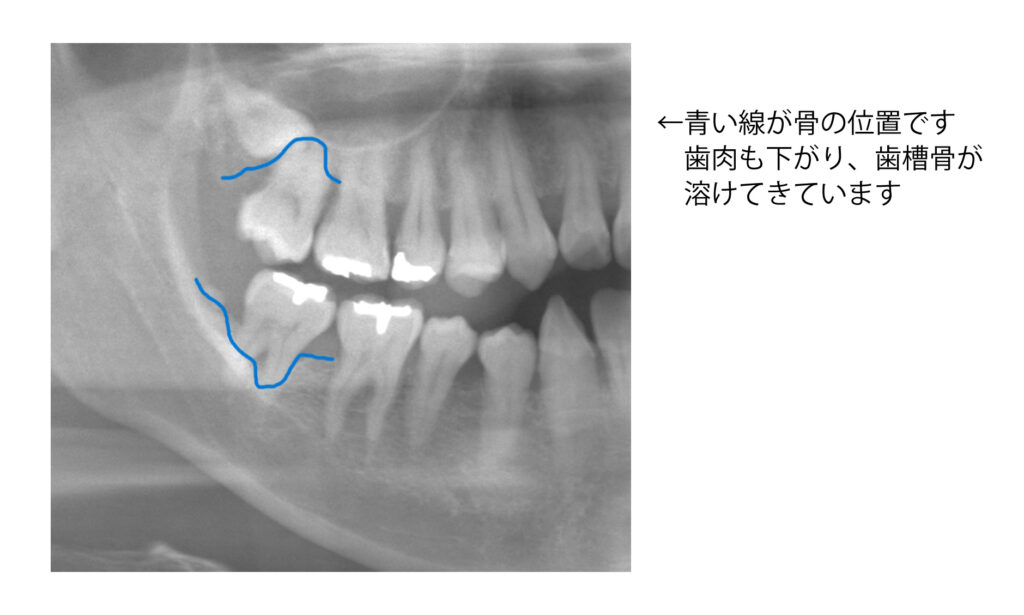

歯周病の厄介な点は、痛みがほぼ出ないことです。歯ぐきの腫れや出血に気づかず放置すると、歯を支える骨(歯槽骨)が少しずつ溶け、最終的には歯が抜け落ちることにもなります。レントゲンや歯肉の検査で骨の状態を確認することが非常に重要です。

初診で来院して下さる患者様の中で、久しぶりの歯医者で痛みもなくクリーニング希望で来られた方が、レントゲンを撮影すると歯周病が進んでいて骨が溶けていることがあります。また痛みが出る虫歯は神経まで達していて大きくなってしまったものが多く、小さな虫歯はあまり痛みがありません。